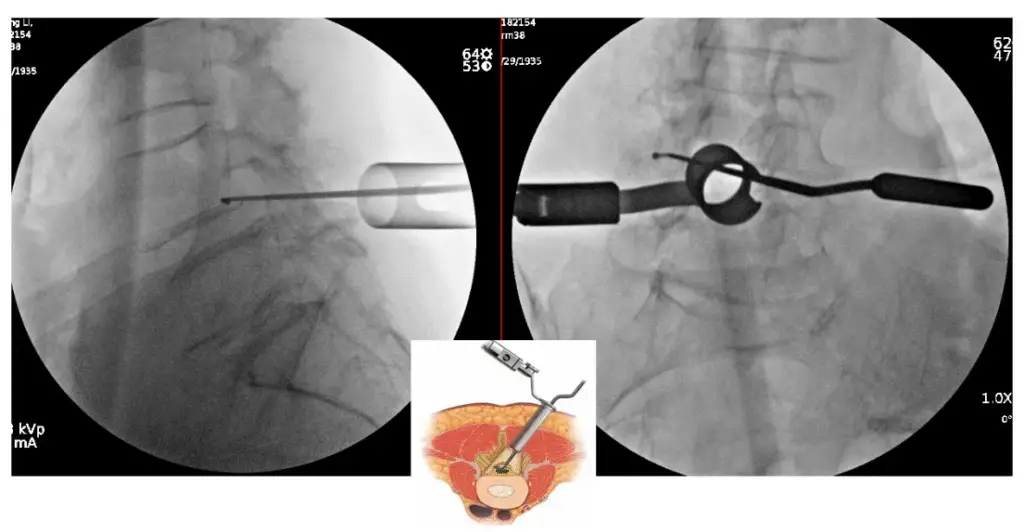

ULBD